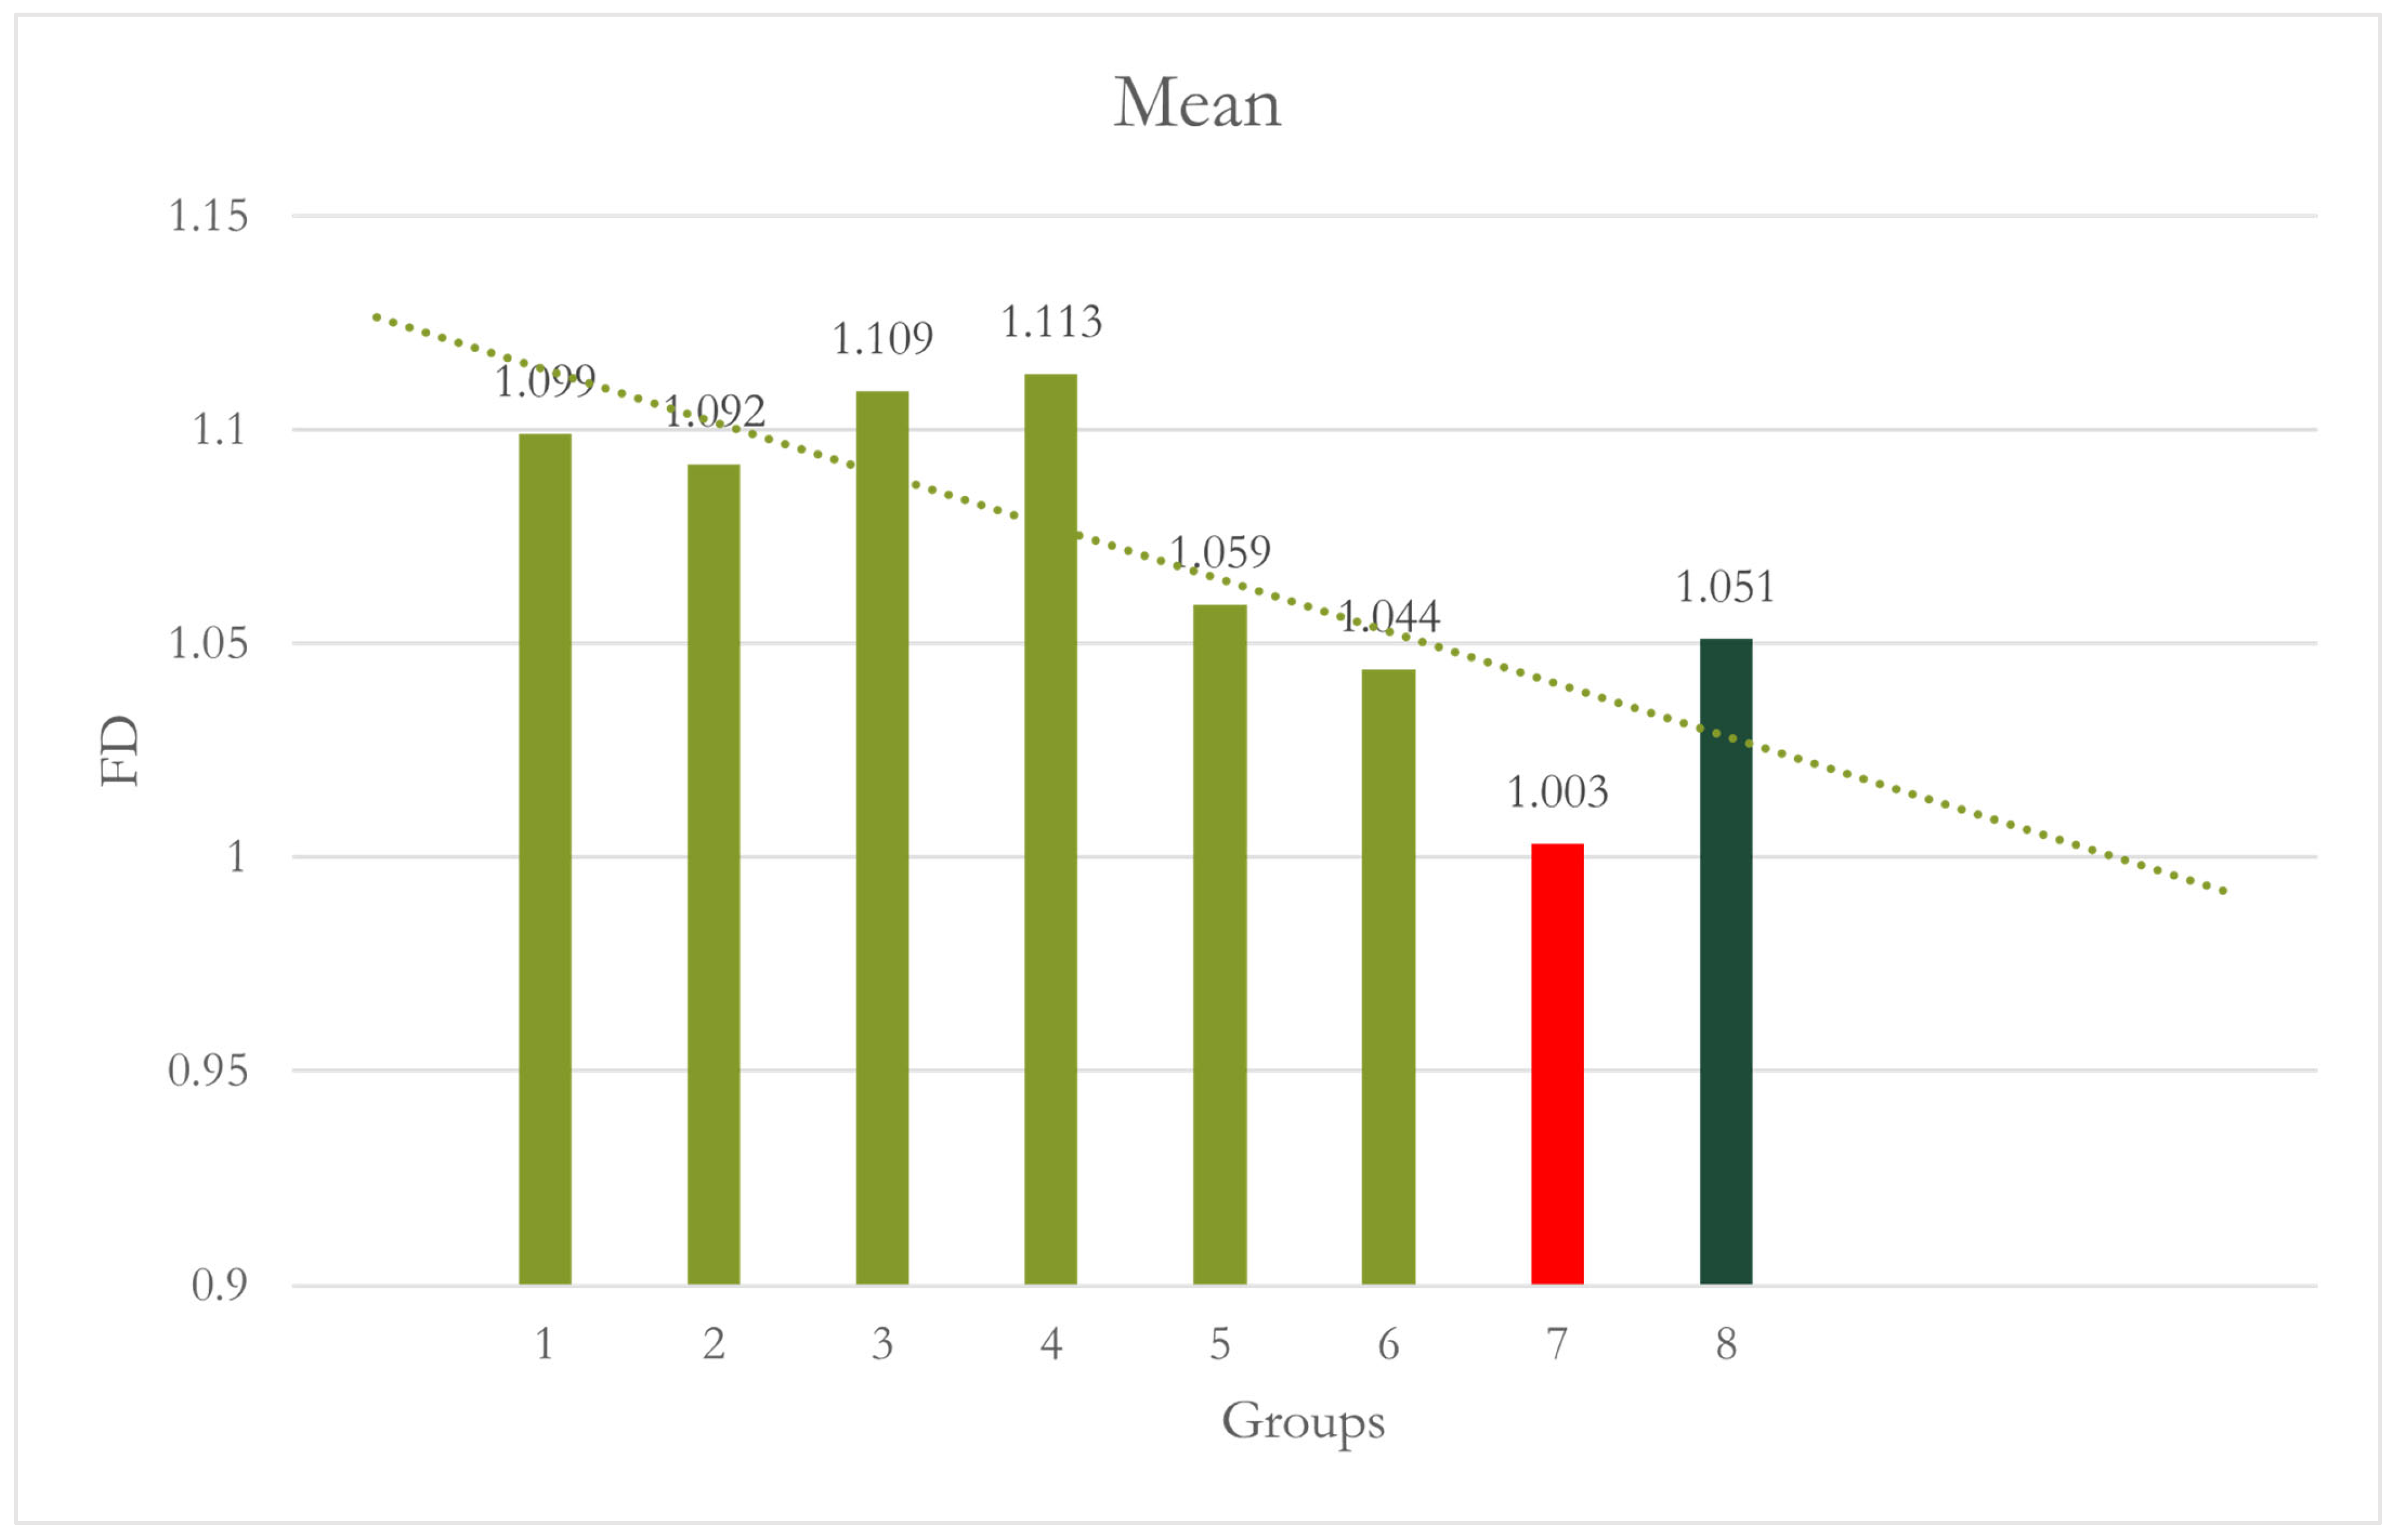

| Site 3 Anterior | 1 | 10 | 1.099 | 0.023 | 0.007 | 1.082 | 1.115 | 1.055 | 1.127 | - | 1.000 |

| 2 | 10 | 1.092 | 0.031 | 0.010 | 1.070 | 1.115 | 1.039 | 1.140 | 1.000 | - | |

| 3 | 10 | 1.109 | 0.030 | 0.009 | 1.088 | 1.130 | 1.067 | 1.149 | 1.000 | 0.992 | |

| 4 | 10 | 1.113 | 0.022 | 0.007 | 1.097 | 1.129 | 1.084 | 1.146 | 0.997 | 0.975 | |

| 5 | 10 | 1.059 | 0.067 | 0.021 | 1.011 | 1.107 | 0.959 | 1.162 | 0.538 | 0.734 | |

| 6 | 10 | 1.044 | 0.063 | 0.020 | 0.999 | 1.089 | 0.924 | 1.105 | 0.152 | 0.277 | |

| 7 | 10 | 1.003 | 0.064 | 0.020 | 0.957 | 1.049 | 0.892 | 1.097 | <0.001 | 0.001 | |

| 8 | 10 | 1.051 | 0.036 | 0.011 | 1.025 | 1.076 | 1.000 | 1.116 | 0.287 | 0.464 | |

| Total | 80 | 1.071 | 0.057 | 0.006 | 1.058 | 1.084 | 0.892 | 1.162 | |||